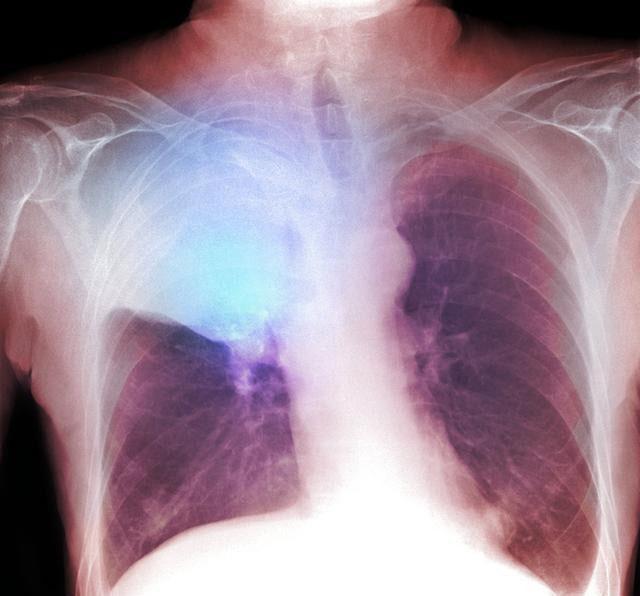

要想早期发现肺癌,必须要做胸部CT定期体检,做胸片并不能及时发现1cm以下的以及隐藏在心脏后面的肺癌结节,胸部CT是发现早期肺癌的最好方法,大于1mm以上的结节都可以通过胸部CT发现,并可以准确的定位肺部结节的位置,测量结节的大小,观察结节的密度,对于某些密度较淡的磨玻璃结节需要考虑手术切除。